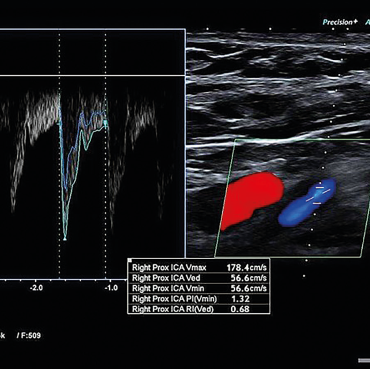

Obr. 2 CT angiografie extrakraniálních a intrakraniálních tepen s významnou kalcifikovanou stenózou pravé ACI ACI – arteria carotis internaMuž, 69 let, dlouholetý kuřák, byl přijat na naše neurologické oddělení pro druhou ataku amaurosis fugax vpravo v průběhu pěti dnů. Přechodnou slepotu popisoval jako náhle vzniklý stav, při kterém měl pocit, že se mu velmi rychle vytvořila clona před pravým okem. Obě ataky prchavé monokulární amaurózy netrvaly déle než 2–3 minuty. Po druhé atace vyhledal očního lékaře, který provedl komplexní oftalmologické vyšetření včetně očního pozadí, optické koherentní tomografie a zorného pole. Nález na předním segmentu oka byl oboustranně přiměřený věku. Na očním pozadí dominovaly změny chronické hypertonické retinopatie. Zorné pole bylo v pořádku. Při přijetí na neurologické oddělení byl neurotopický nález v normě. Dle anamnézy se měl pacient léčit pro arteriální hypertenzi a hyperlipidemii, ale léky přestal užívat, protože se cítil zdráv. Při vstupním měření krevního tlaku byly zjištěny hodnoty 200/100 mm Hg. Akce srdeční byla pravidelná a vstupní elektrokardiografické vyšetření (EKG) doložilo sinusový rytmus. Fibrilace síní nebo jiná arytmie nebyly zachyceny ani při monitoraci EKG během hospitalizace na neurologické jednotce intenzivní péče (JIP). Glykemický profil byl v normě. Při vyšetření koncentrace lipidů v krvi byla zjištěna hypercholesterolemie s hodnotou LDL cholesterolu 2,94 mmol/l. Vyšetření mozku pomocí CT neprokázalo známky akutního krvácení či ischemie (obr. 1). Dle současně provedené CTA mozkových tepen byla zjištěna významná stenóza pravé ACI, nicméně hodnocení jejího stupně bylo modifikováno výraznějšími kalcifikacemi (obr. 2). Vzhledem k tomuto nálezu byla ke korelaci s CTA doplněna duplexní sonografie extrakraniálních tepen, která potvrdila 80–85% stenózu pravé ACI (obr. 3, 4). Dle transkraniální barevně kódované duplexní sonografie (TCCS) byly morfologie a hemodynamické poměry intrakraniální cirkulace v normě, nebyly zachyceny ani mikroembolické signály. V léčbě byly indikovány kyselina acetysalicylová 100 mg denně (nejprve podána nasycující dávka 300 mg) a CEA. Současně byly nasazeny atorvastatin v dávce 80 mg denně a inhibitor angiotenzin konvertujícího enzymu (ACE) v léčbě arteriální hypertenze.

Obr. 3 Duplexní sonografie s obrazem symptomatické stenózy pravé ACI 80–85 % ACI – arteria carotis internaDruhý den po přijetí byl pacient přeložen na Neurochirurgickou kliniku KZ, a.s. – Masarykova nemocnice v Ústí nad Labem. V regionální anestezii byla provedena endarterektomie odstupu pravé ACI. Výkon proběhl bez komplikací a pacient byl třetí pooperační den propuštěn do domácí péče. Kon­trolní duplexní sonografická vyšetření provedená v naší neurosonologické laboratoři v průběhu tří, šesti a 12 měsíců po operaci prokázala normální průtok v ACI, bez známek restenózy. Při půlroční i roční klinické kontrole byl pacient bez potíží, bez recidivy amaurosis fugax či jiné TIA nebo iCMP.